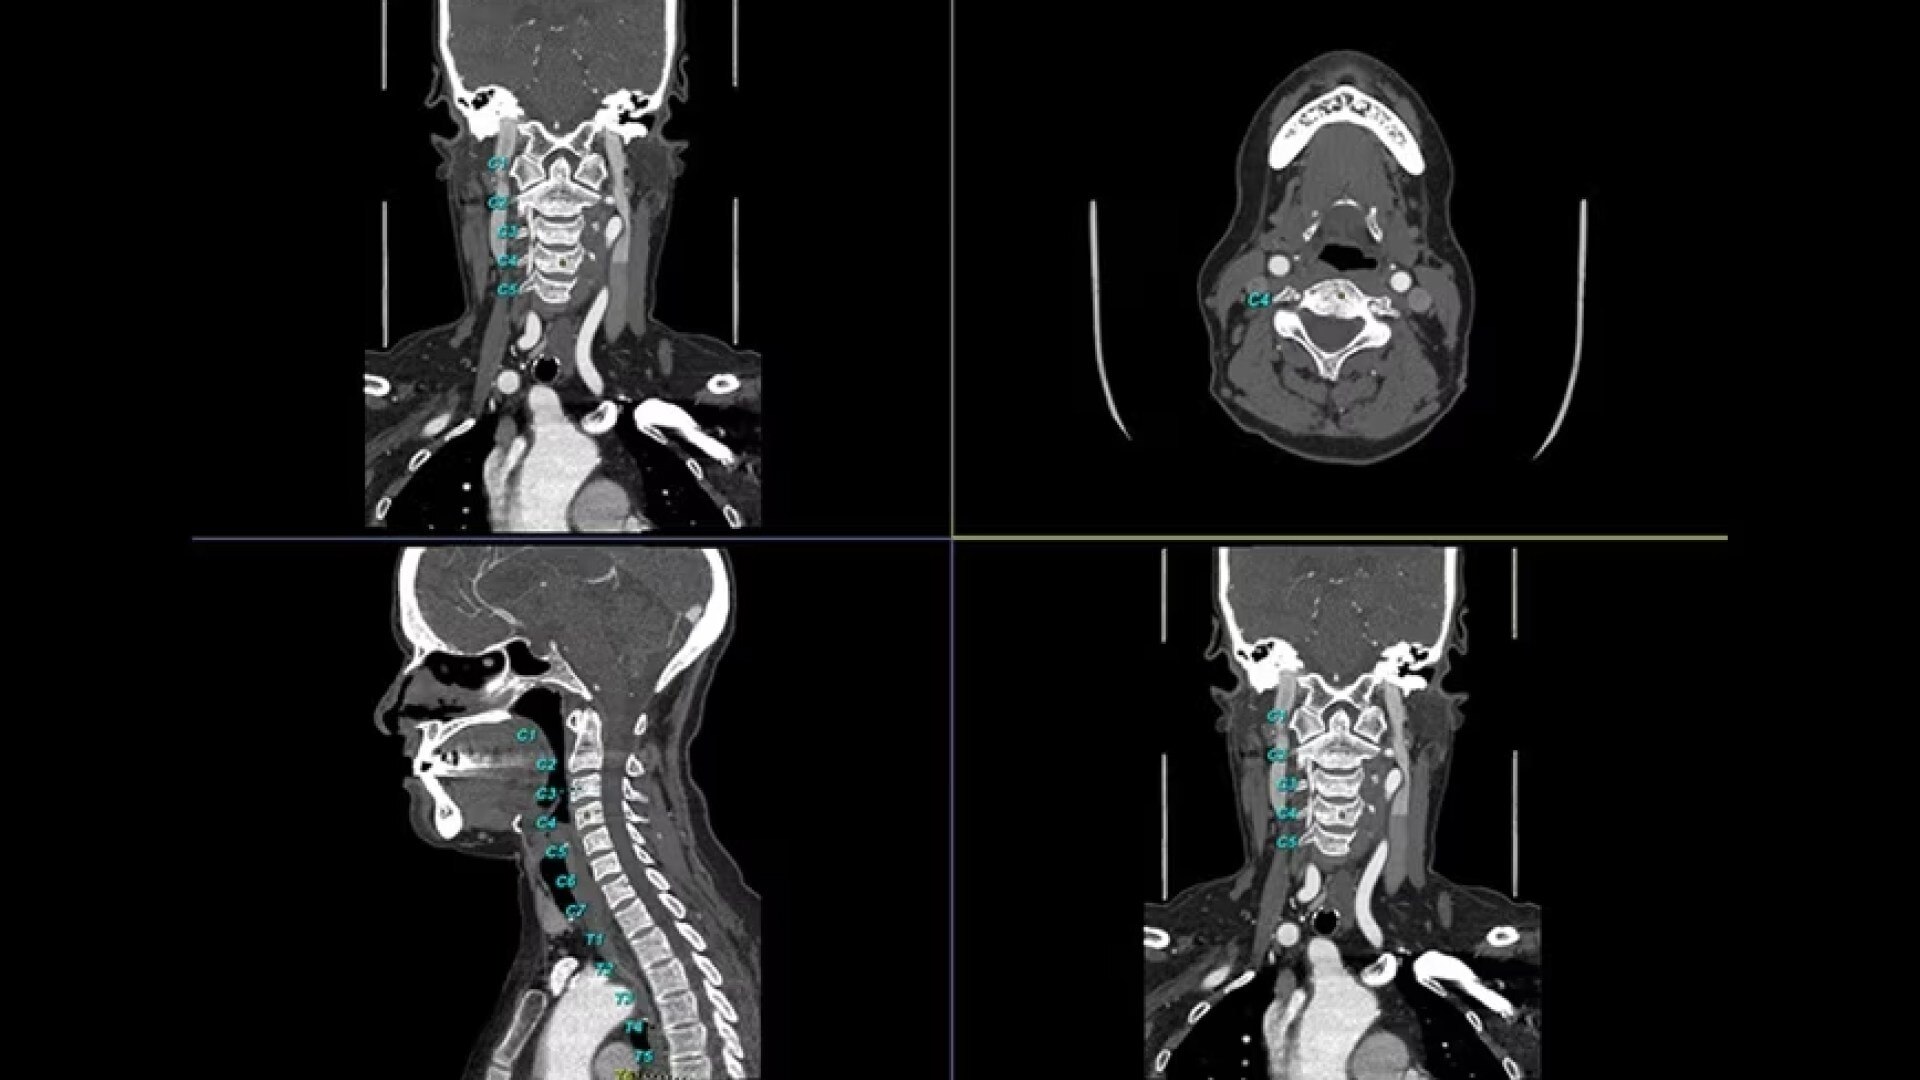

Bone VCAR

Spine assessment with deep-learning based CT application.

Automated spine identification and labelling.

>90% labeling accuracy based on Deep learning algorithm trained on global datasets acquired with a broad range of acquisition parameters.

• Automated spine labeling